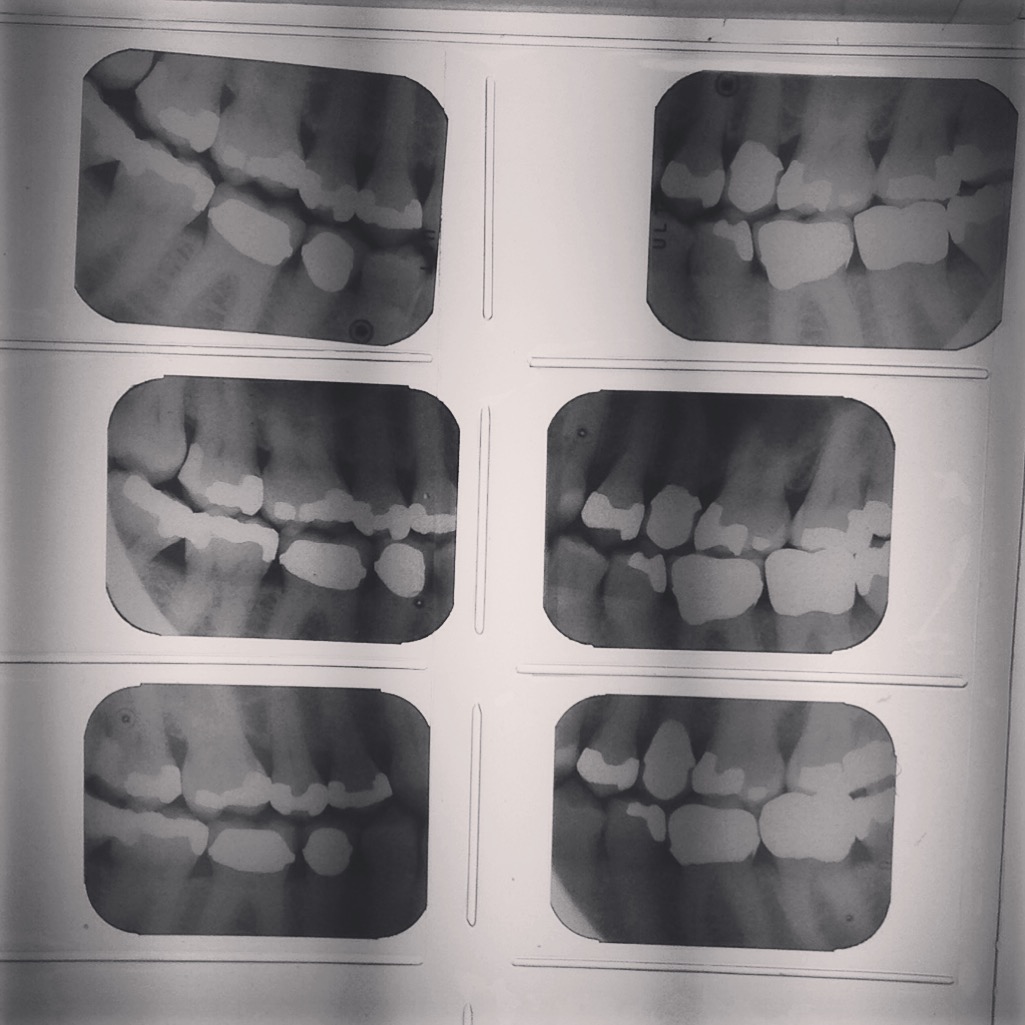

Halloween is coming and I’m so excited I must say. So once again I’ll be celebrating by posting random spooky stuff until October 31. Let’s begin with these X-rays of my teeth, if only because I spent so much at the dentist’s last week that I might as well get my money’s worth out of it.